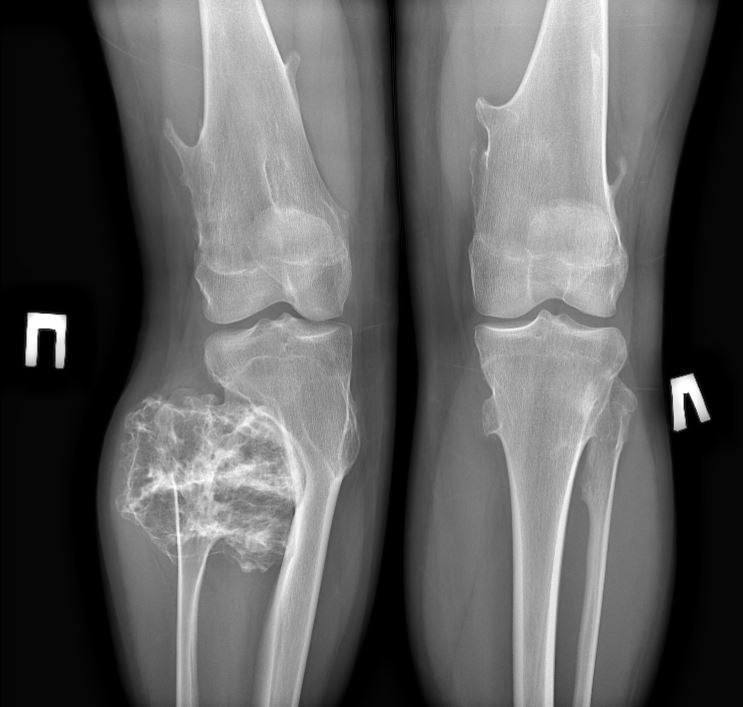

В МОДКТОБ обратились родители 15-летнего юноши с жалобой на твёрдое новообразование в области малоберцовой кости. Обследование показало остеохондрому — доброкачественный костный вырост.

Размер опухоли достигал 988 см, поэтому врачи приняли решение о плановой операции. Новообразование удалили в пределах здоровой костной ткани.